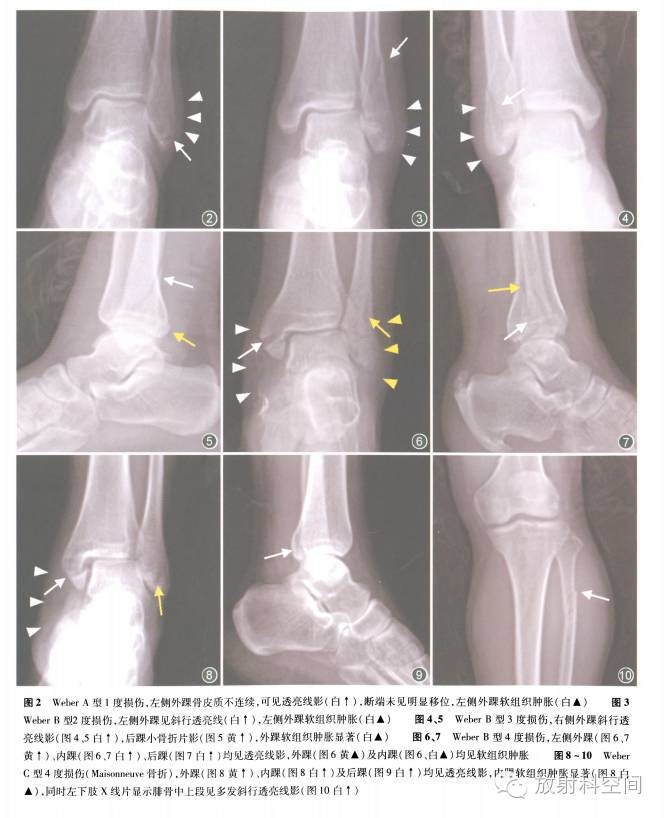

对应Lauge-分型,骨折是由于旋后内收力所造成。外踝承受了过度的张力,导致韧带拉伸,进而发生撕脱骨折。l度损伤时下胫腓联合平面以下韧带断裂或外踝撕脱,X线片表现为外踝的横行骨折,外踝软组织肿胀(图2),可给予石膏固定保守治疗,效果与手术治疗无差别。

对应Lauge-分型,骨折是由于旋后外旋力所造成。1度损伤为胫腓前韧带断裂,X线片通常无异常所见。2度损伤时距骨更加外翻,脚处于旋后状态,将导致腓骨斜行或螺旋行骨折,X线片上清晰可见,外踝软组织肿胀(图3),斜行骨折是典型的Weber B型骨折,这种骨折常起白踝关节距骨穹窿水平的中部,但也可能起白上方几厘米层面。

3度损伤为外踝骨折片后移,导致胫腓后韧带产生张力,伴有后踝的断裂或撕脱(图4、5)。4度损伤为骨折片更加后移,导致内侧面产生极大张力,三角韧带断裂或者于横断面上牵拉内踝,X线片表现为i踝骨折(图6、7),伴内、外踝软组织肿胀。

典型的Weber B型骨折在标准正位X线片显示胫骨远端与腓骨远端间隙增宽,提示胫腓前韧带断裂,下胫腓联合水平见腓骨斜行骨折。前后位及侧位X线片上可见后踝骨折,内踝与距骨间间隙增宽提示i角韧带断裂。3 -4度损伤固定内、外踝后,踝关节稳定性即可恢复,如果后踝骨块较小而且白行复位、下胫腓联合无分离,可不固定后踝及下胫腓联合,否则需要对两者进行复位同定以恢复踝穴正常结构。

对应Lauge-分型,骨折是由于旋前外旋力或旋前外展力所造成。l度损伤为内踝撕脱或三角韧带断裂,由于旋前,内侧产生最大张力,可造成三角韧带断裂或是内踝撕脱。此时若损伤停止,可能仅有三角韧带的断裂或是内踝的撕脱。而在多数情况下,损伤进一步发展。2度损伤为胫腓前韧带断裂;3度损伤为下胫腓联合上方水平腓骨骨折,为典型的Weber C型骨折。多数病例X线片可见,但一些病例因骨折位置较高,只有在小腿X线片中可见改变,这种骨折类型也称作骨折(图8-10),漏诊率较高,达39%。4度损伤为胫腓后韧带断裂或后踝撕脱,也称为后踝骨折。X线片显示内侧间隙轻度增宽,但是基于Lauge-分型理论,此时一定存在三角韧带断裂。腓骨、内踝复位固定,后下胫腓联合往往仍存在分离,踝穴增宽,踝关节仍然不稳定,还应对下胫腓联合进行复位及固定。手术顺序是固定腓骨、复位下胫腓联合、后踝、内踝,固定下胫腓联合。有研究统计下胫腓分离如未及时纠正,踝关节创伤关节炎将会在伤后3个月-6年时发生。

四、如何阅片、诊断

了解踝关节骨折损伤的顺序,才能知道如何去寻找骨折以及根据软组织影像表现提示韧带损伤情况。例如,后踝骨折作为一个单纯性骨折而言并不常见,依据分型系统,我们发现大多数的后踝骨折属于Weber B型或C型骨折,或者是Weber B型3度损伤,或者是Weber C型4度损伤。如此时踝关节X线片上没有外踝骨折征象,我们将其定为Weber B型骨折,但仍然有型4度损伤的可能,例如三角韧带断裂或撕脱,高位腓骨骨折以及后踝骨折。若X线片上显示内踝软组织肿胀提示内踝撕脱,而小腿的X线片又显示高位腓骨骨折,综合结果最终可将其诊断为型4度损伤(图8 -10),此种骨折属于不稳定性踝关节骨折,需要手术修复。